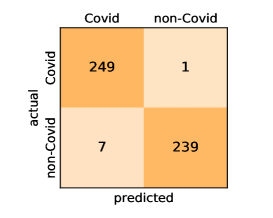

Here, we present and discuss the obtained results for detecting COVID-19 on the considered CT image datasets with different deep networks. We report the quantitative results along with the confusion matrices for every single architecture of the adopted networks.

On the SARS-CoV-2 CT dataset, ResNet101 achieves the best overall performance with respect to almost all evaluation metrics, with an average accuracy and F1-score of and , respectively. The model also achieves an average sensitivity rate of indicating that, on average, only two COVID-19 images are falsely predicted as negatives. It is also powerful enough to correctly identify all Non-COVID-19 cases with only one false positive resulting a specificity rate of . The highest sensitivity score of is achieved by the InceptionV3 model, where only one COVID-19 image is falsely predicted as negative on average. The SqueezeNet model obtains the lowest performance with respect to all evaluation metrics with a fairly acceptable average accuracy and sensitivity scores of and , respectively. Also the ShuffleNet architecture obtains satisfactory performance with approximately improvements on average for all metrics compared with SqueezeNet. Although the results obtained by these models are inferior compared with the rest of models, but they are more efficient. This matches their main objective of reducing the computational costs rather than improving their visual recognition abilities. The rest of models achieve competitive performance and very promising results with slight performance differences. Comparing the different variants of ResNet and DenseNet, we can see that the deeper variants from each architecture yield a slightly better performance. The deeper ResNet101 and ResNeXt101 show a marginal gain in performance compared with their shallower counterparts. The details about class-wise results for each model are summarized in the confusion matrices in Figure 9.